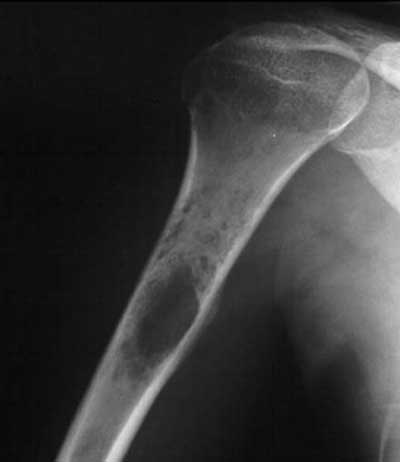

استئوسارکوم بیشتر در افراد کم سن و سال ایجاد می شود و به سرعت به قسمت های دیگر بدن نفوذ می کند. محل تشکیل این تومور نیز در بالا و پایین زانوها و شانه ها به خصوص در استخوان های بلند این نواحی است. قابل ذکر است که این تومور در صفحات رشد استخوان های ناحیه های ذکر شده ایجاد می شود.

سارکوم یوئینگ بیشتر در استخوان های نرم و بلند بازوها و پاها ایجاد می شود و کودکان و نوجوانان و به طور کلی افراد کم سن و سال بیشتر در معرض ابتلا به این نوع تومور بدخیم هستند.